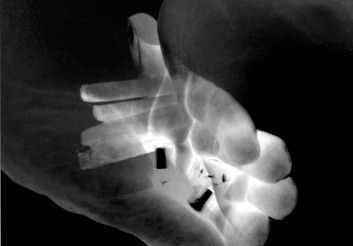

Photography:

Jennifer Braun